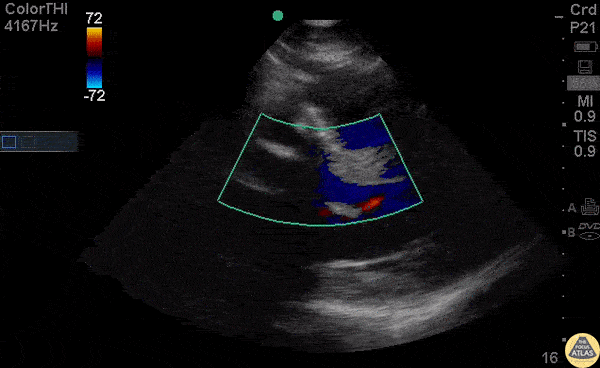

Parasternal long view with color doppler of a young male presenting with chest pain and a history of surgically corrected truncus arteriosus including an aortic valve replacement. Notable here is the regurgitant jet just above the aortic outflow tract. The etiology of this jet is uncertain but could represent a persistent VSD despite correction. Dr. Bryan Jarrett - Kings County Emergency Medicine